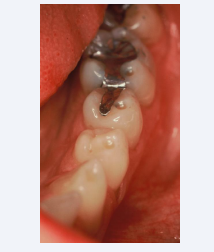

Deformations of Restorative Materials

Fatigue easily manifests itself in prostheses and restorative materials such as amalgam and acrylic. Termed Luder Lines or molecular slip bands, the molecules in the alloy are rearranging themselves under the influence of compressive strain (Figures 5 and 6). One can demonstrate the effect by bending a metal coat hanger back and forth and examining the stress configuration that is produced [8].

Fatigue in Acrylic appears as wavy lines or sets (Figures 7 and 8).